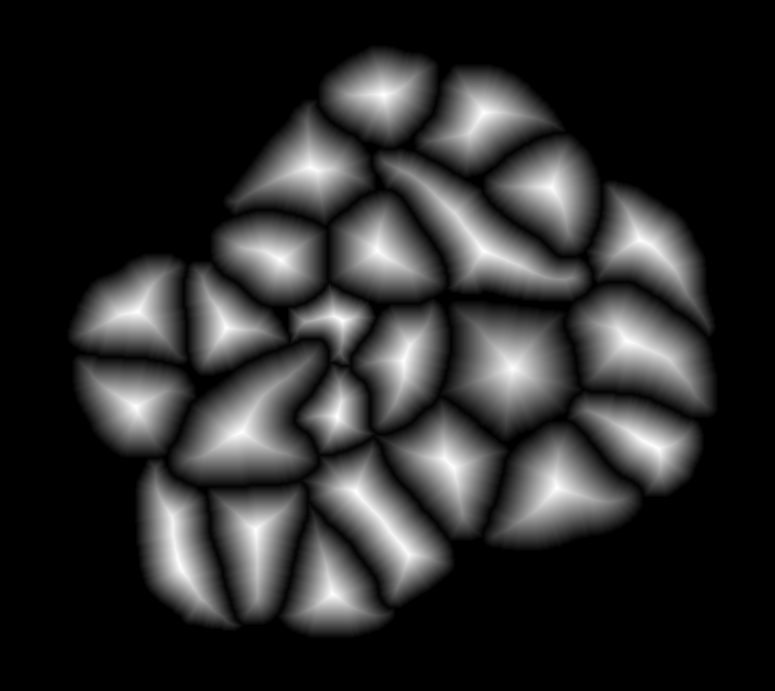

![]() |

| (a) | (b) |

| (c) | (d) |

For an example subimage given in Fig. 2a, these distance definitions are illustrated in Figs. 2b and 2c, respectively. The inner distance definition well indicates the cell centers since it uses the Euclidean distances from pixels to their closest cell centers. However, as it uses the centers as the reference point, the distance decrease from a center to its boundaries is the same for all directions and for all cells. Thus, when it is used alone, this definition imposes a circular and one-sized shape on the cells, as also seen in Fig. 2b. On the contrary, since the normalized outer distance is calculated with a reference to a cell boundary, this decrease may differ from one direction to another as well as from one cell to another, depending on the shape and size of the cell. Thus, it better preserves the morphological characteristics of cells, as seen in Fig. 2c.